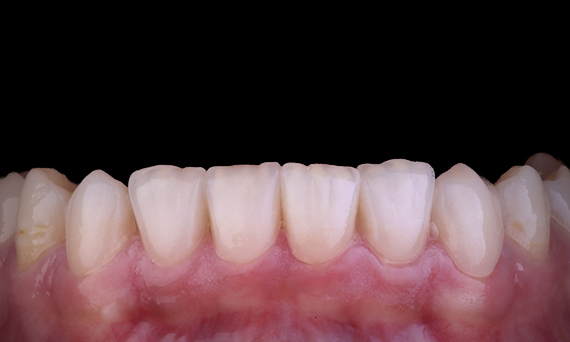

Casos clínicos

Los médicos de todas partes de Australia y Nueva Zelanda comparten amablemente presentaciones relevantes, interesantes y, a veces, desafiantes para los pacientes, junto con su selección de materiales y métodos para optimizar los resultados de sus pacientes.

En Dentsply Sirona, cada día destacamos a profesionales dentales de todo el mundo para que brinden a millones de pacientes un mejor cuidado dental y hagan sonreír a las personas. Nuestro enfoque de caso clínico se trata de compartir estas sonrisas, que los médicos de Australia y Nueva Zelanda han creado, con la comunidad dental en general.